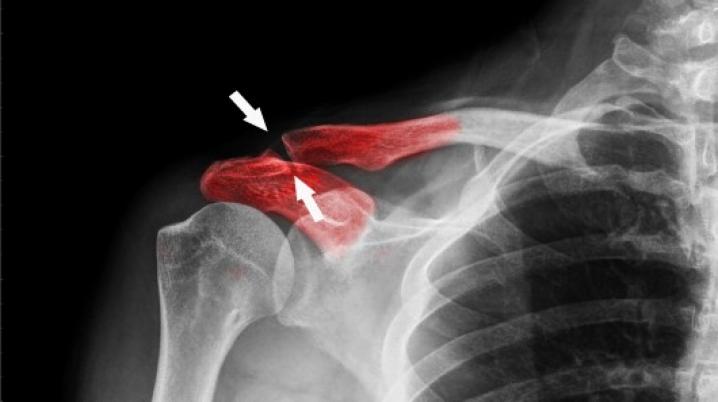

При сложных переломах и срастании протеза костный трансплантат зачастую нужно тщательно восстанавливать механическим путем. Его удаление может быть весьма болезненной процедурой и дальнейшая механическая стимуляция для регенерации кости после операции становится проблематичной, если пациенту строго запрещено двигаться. При решении этих задач ученые обнаружили, что наночастицы с протеинами, направленные к месту травмы магнитным путем, помогают стимулировать клетки для регенерации кости.

Однако, осложнения, запрещающие пациенту двигаться, исключают применение этой терапии. Например, при повреждении скелетной структуры у человека не хватает костей для пересадки, поэтому его реабилитация проходит очень медленно, и не всегда заканчивается полным успехом.

Учеными из Кильского университета и Ноттингема был испытан метод с магнитными наночастицами. По их словам, материал можно направить прямо к месту травмы без хирургического вмешательства. Это дает возможность на расстоянии управлять наночастицами, доставляющими стволовые клетки, в процессе восстановления кости.